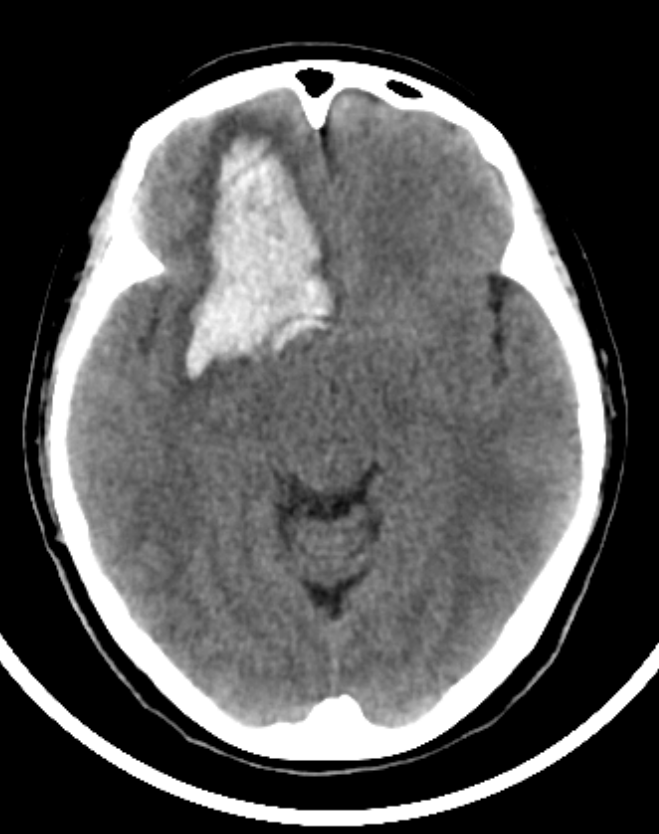

前交通动脉瘤没有理想的夹子,又想保护粘在动脉瘤上的一根静脉,采用头端可调持夹钳,左手把夹子送到位稳住,右手用剥离子调整夹子角度。